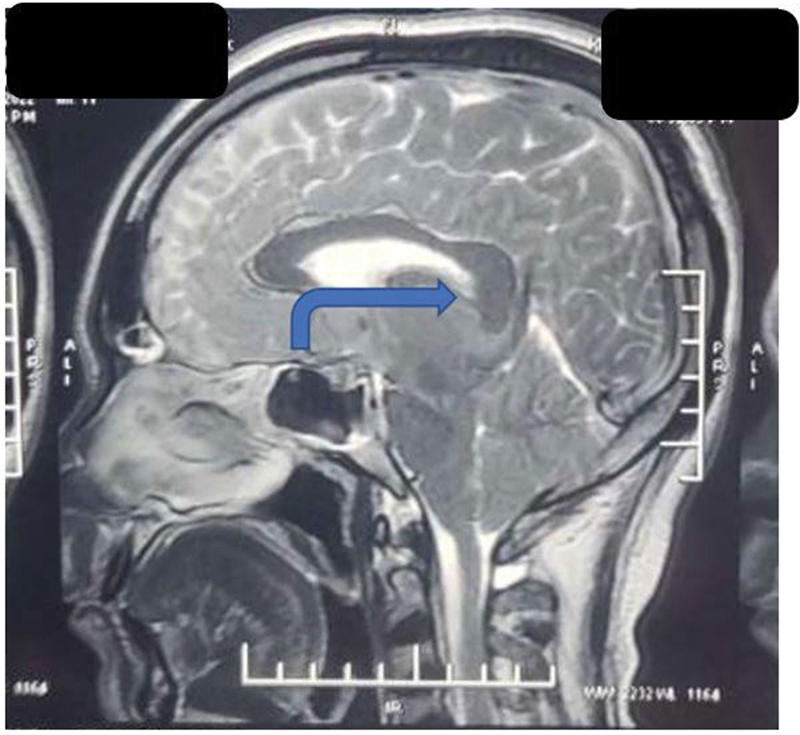

Cerebrospinal fluid (CSF) provides buoyant support to the brain and spinal cord. According to the Monroe-Kellie doctrine, confined space in the cranium causes any change in CSF volume contributing to significant intracranial pressure changes, which cause a variety of pathologies and symptoms. We, hereby, present a case of a 33-year-old gentleman who after a motorcycle road traffic accident came to us complaining of persistent headache and neck pain with subdural hematoma (SDH) like presentation, clinically and radiologically, but was reevaluated and diagnosed as traumatic intracranial hypotension and successfully managed surgically after that. Hygromas are believed to be compensatory enlargement of the subdural space due to the loss of CSF volume. The true mechanism of the development of SDH or hygroma due to intracranial hypotension is yet to be hypothesized but provisionally described by a rupture of the bridging veins by being pulled away from the dura because of the low intracranial pressure (ICP) and brain descent. Many prior cases in the literature are shown to have treated the patient with immediate burr hole and decompression of SDH, but this paradoxically worsens the patient due to further lowering of ICP. The causes of prolonged postconcussion headaches are often unidentified, of which intracranial hypotension caused by a CSF leak is potentially under-recognized. In such cases, bilateral SDH with mass effect must be ruled out of any CSF leak before attempting the lifesaving decompressive surgery, as it may paradoxically lead to further morbidity and mortality of the patient.